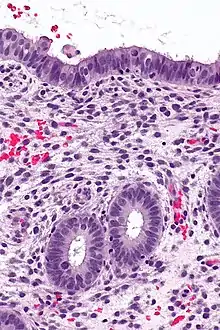

![]() | Mucinous cystadenoma | Micrograph showing Mucinous Cystadenoma of ovary. The cyst wall is lined by tall columnar epithelium and filled with mucin. | Category: Histopathology of mucinous cystadenoma | Mucinous cystadenoma |